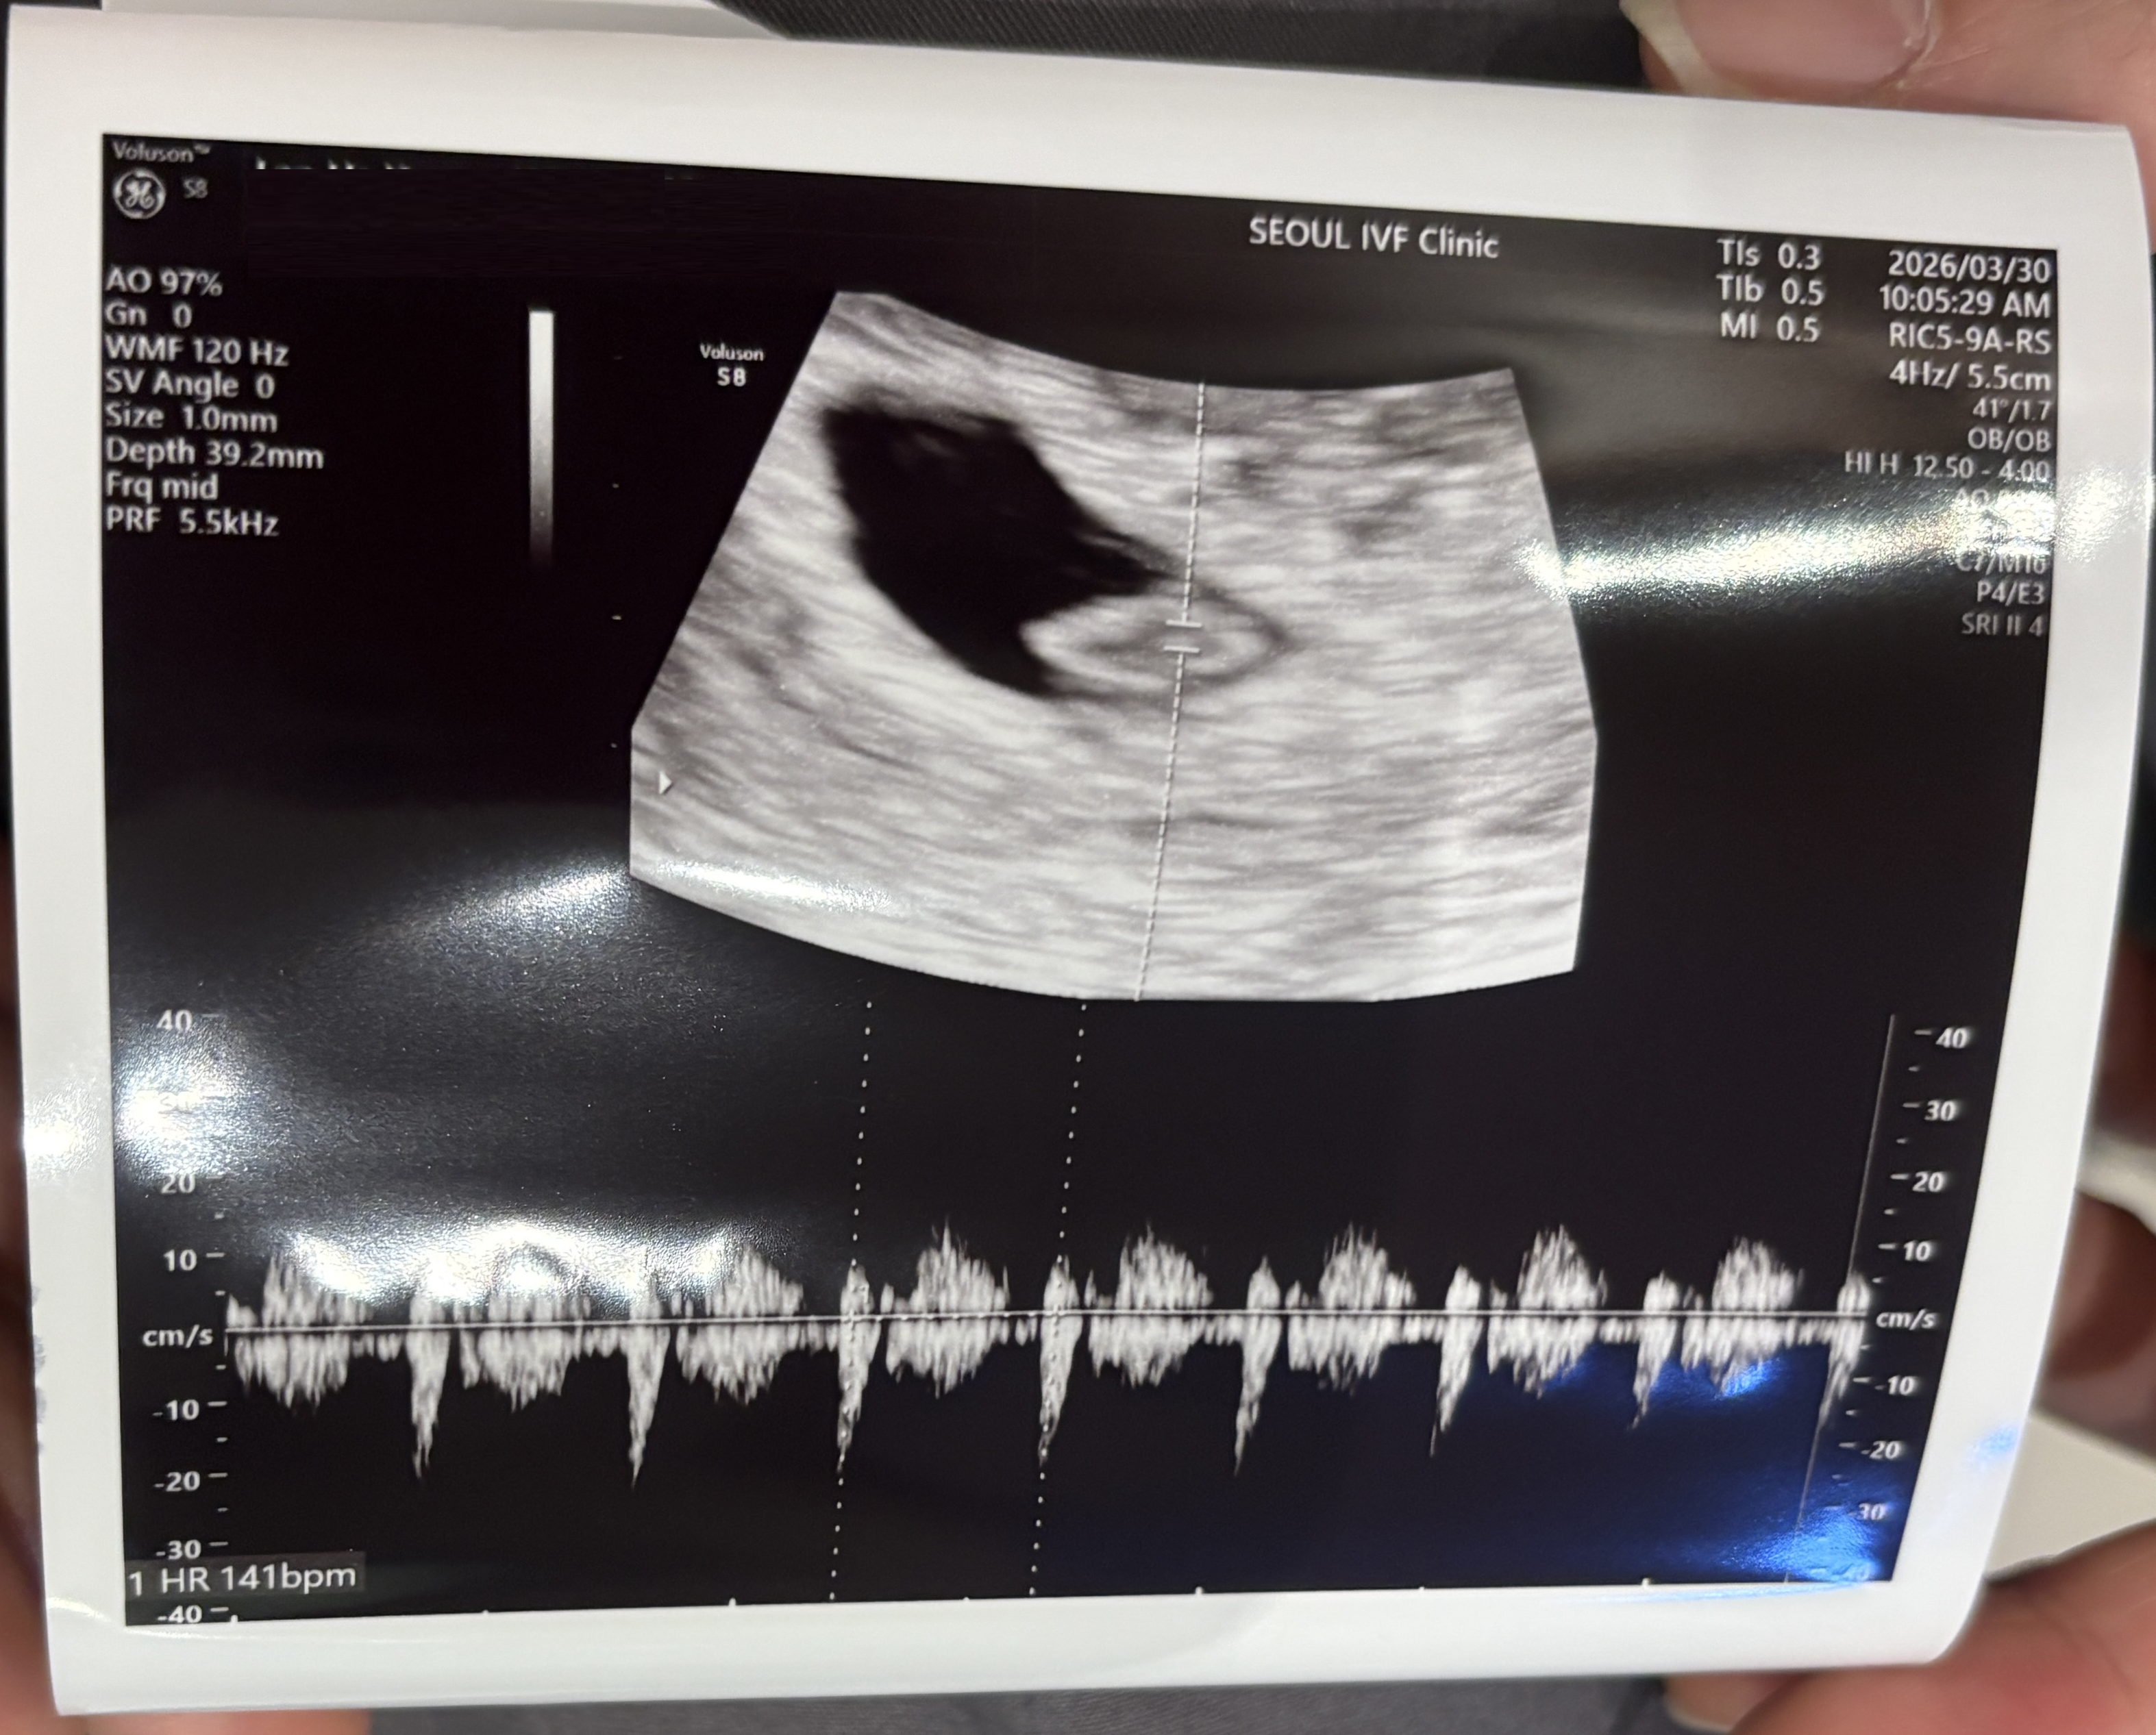

| 가슴 떨리는 임신 이야기를 공유해 주세요. | 이경훈 원장 덕분에 한 번의 시도로 임신에 성공하게 되었습니다. 초음파를 통해 아기의 심장 소리를 확인했을 때 정말 큰 감동을 느꼈습니다. |